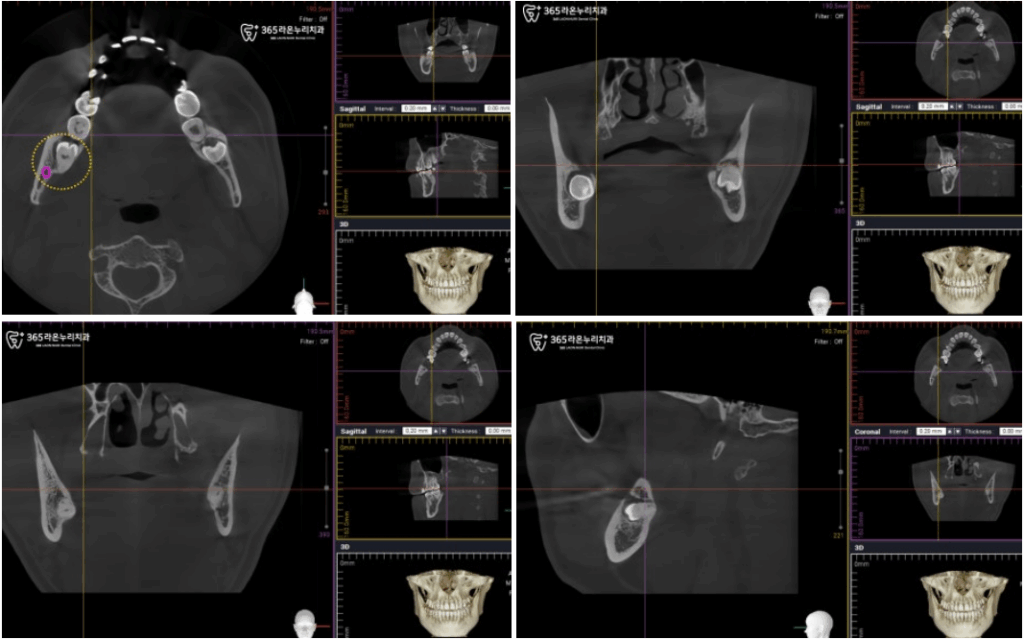

그렇기 때문에 정확한 진단은 필수입니다.

엑스레이 사진에서 치아와

닿아 있지 않아도 위치 상

겹쳐 보일 수 있기에, 신장동

치과 에서는 CT 촬영 후

재판독하였습니다.

CT를 찍어 신경과의 관계를

알아보고 닿지 않은 채

근접해 있는 것으로만

진단되어, 사랑니 발치를

진행하기로 했습니다.

엑스레이를 찍어보고

손상으로 인한 감각 이상 가능성이

있다고 생각된다면 CT를 찍어

신경과의 관계를 알아보는 것이 중요합니다.